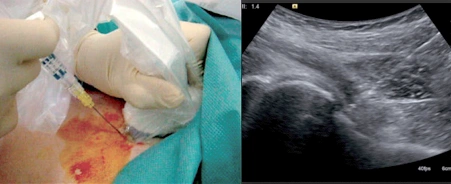

Queste infiltrazioni vengono somministrate dal radiologo interventista, che utilizza tecniche di imaging come ecografia, fluoroscopia o TAC per guidare con precisione l’iniezione del farmaco direttamente nell’articolazione interessata. Il trattamento, che dura solo pochi minuti, è generalmente ripetibile in base alle necessità individuali del paziente. La letteratura scientifica ha dimostrato l’efficacia di queste infiltrazioni, che sono particolarmente utili per migliorare i sintomi e la qualità della vita nei pazienti con osteoartrosi.

L’immagine dimostra l’iniezione percutanea di farmaco per via eco-guidata effettuata dal radiologo interventista. Sulla sinistra l’ago contenente il farmaco e la sonda ecografica, sulla destra l’immagine in diretta della punta dell’ago nella zona desiderata